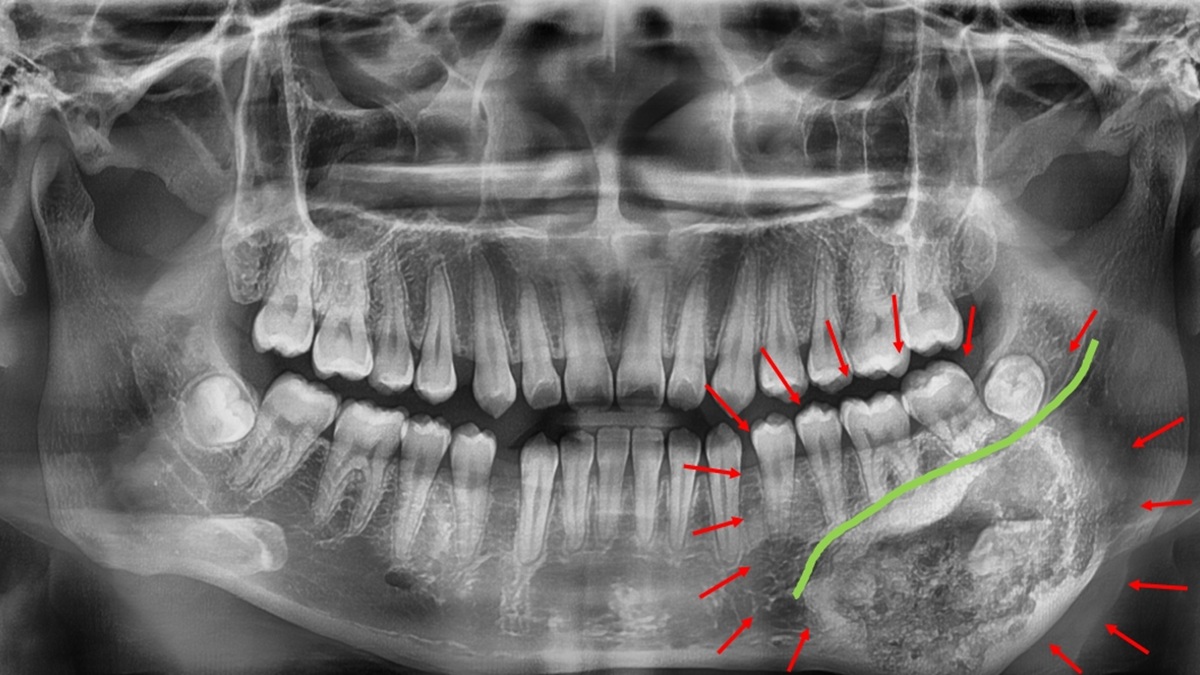

▲經影像與病理切片檢查後,確診為罕見的良性齒源性腫瘤–牙骨質骨化纖維瘤。(圖/記者蕭麗鳳攝)

林楠瑾醫師說,牙骨質骨化纖維瘤的邊界常與正常骨質交錯,若手術切除不夠精準,可能傷及下顎齒槽神經或造成顎骨變形。為提高手術安全與精準度,術前以3D列印技術製作出患者顎骨立體模型,模擬腫瘤切除範圍與骨骼重建角度。透過3D列印手術導引版輔助,醫師得以清楚辨識神經走向與腫瘤邊界,規劃最理想的手術路徑,在完整切除腫瘤的同時成功保留下顎齒槽神經,維持下唇感覺與口腔功能。